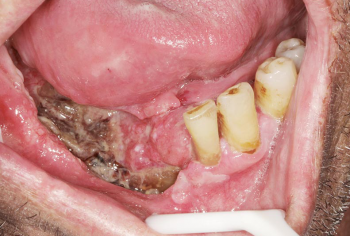

Article réservé à nos abonnés Une histoire de HPV !

CAS 1 Motif de la consultation. Patientde 48 ans venu consulter pour une lésion sur la pointe de la langue....